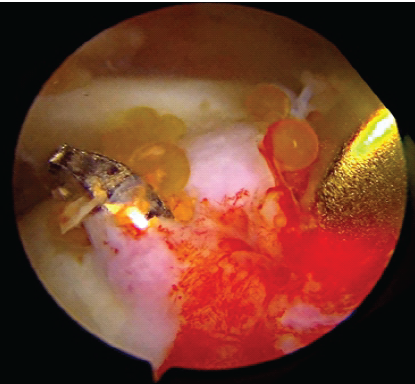

An ACL jig, equipped with a tip aimer, is then meticulously introduced through the lateral portal, with a far lateral portal subsequently created to precisely guide the bullet of the ACL jig for accurate tunnel placement. A beath pin is then drilled with precision to ensure its exit at the humeral ridge, establishing the exact trajectory for the subsequent reaming process (Fig. 2).

Figure 2: Beath pin drilled through anterior cruciate ligament jig.

Over this beath pin, a 4.5 mm cannulated reamer is meticulously utilized to create a bone tunnel, through which a Prolene shuttle loop is subsequently passed and retrieved into the joint, facilitating suture management (Fig. 3 and 4).

Figure 3: Beath pin exiting at humerus ridge.

Figure 4: Prolene loop shuttle.